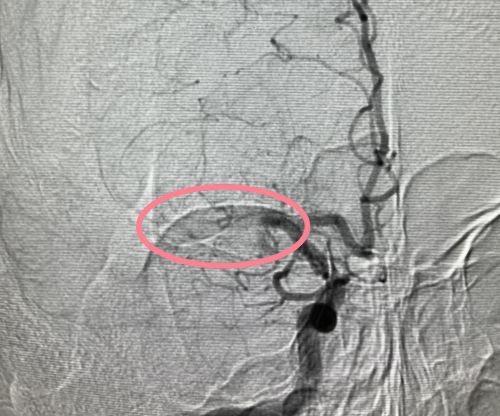

血栓堵塞大脑中动脉。

省医介入血管外科刘放其副主任医师等为患者进行脑血管造影及取栓手术。